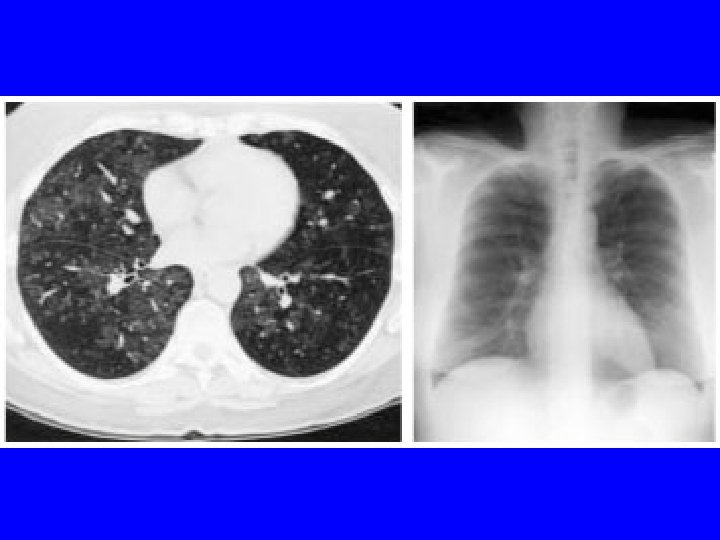

CTA if another episode. She called the next day after a worse episode of tightness, SOB, and hemoptysis. CTA 2/17/04 “tree in bud bilateral and diffuse” suggesting infection or inflammation. Bronchoscopy 2/18/07 appeared normal, with biopsies revealing “mild chronic inflammation. ” March 4 received report of outpatient sputum growing an AFB, and I assumed MAC, and discussed Abx therapy. She then decided on VATS OLBx. (Bronch and OLBx cultures were both negative ultimately. )

Lung biopsy revealed chronic bronchiolitis/ hypersensitivity pneumonitis (extrinsic allergic alveolitis) with opinion from Mayo Clinic path arriving on 3/30/04. “Hot tub lung due to MAC”. I recommended Prednisone 20 mg. daily, but she had major psychiatric complications for which Seroquel was added and prednisone reduced. X-ray, spirometry, and symptoms resolved. Prednisone tapered and stopped in late May. Recurrence of symptoms and rash in August/September.

HP -CT Findings • • • Ground glass opacities Poorly defined centrilobular nodules Mosaic attenuation on inspiration Air trapping on expiration Reticulation (fibrosis) when chronic Silva CI, Churg A, Muller NL. Hypersensitivity pneumonitis: spectrum of highresolution CT and pathologic findings. Am J Roentgenol 2007; 188: 334 -44.